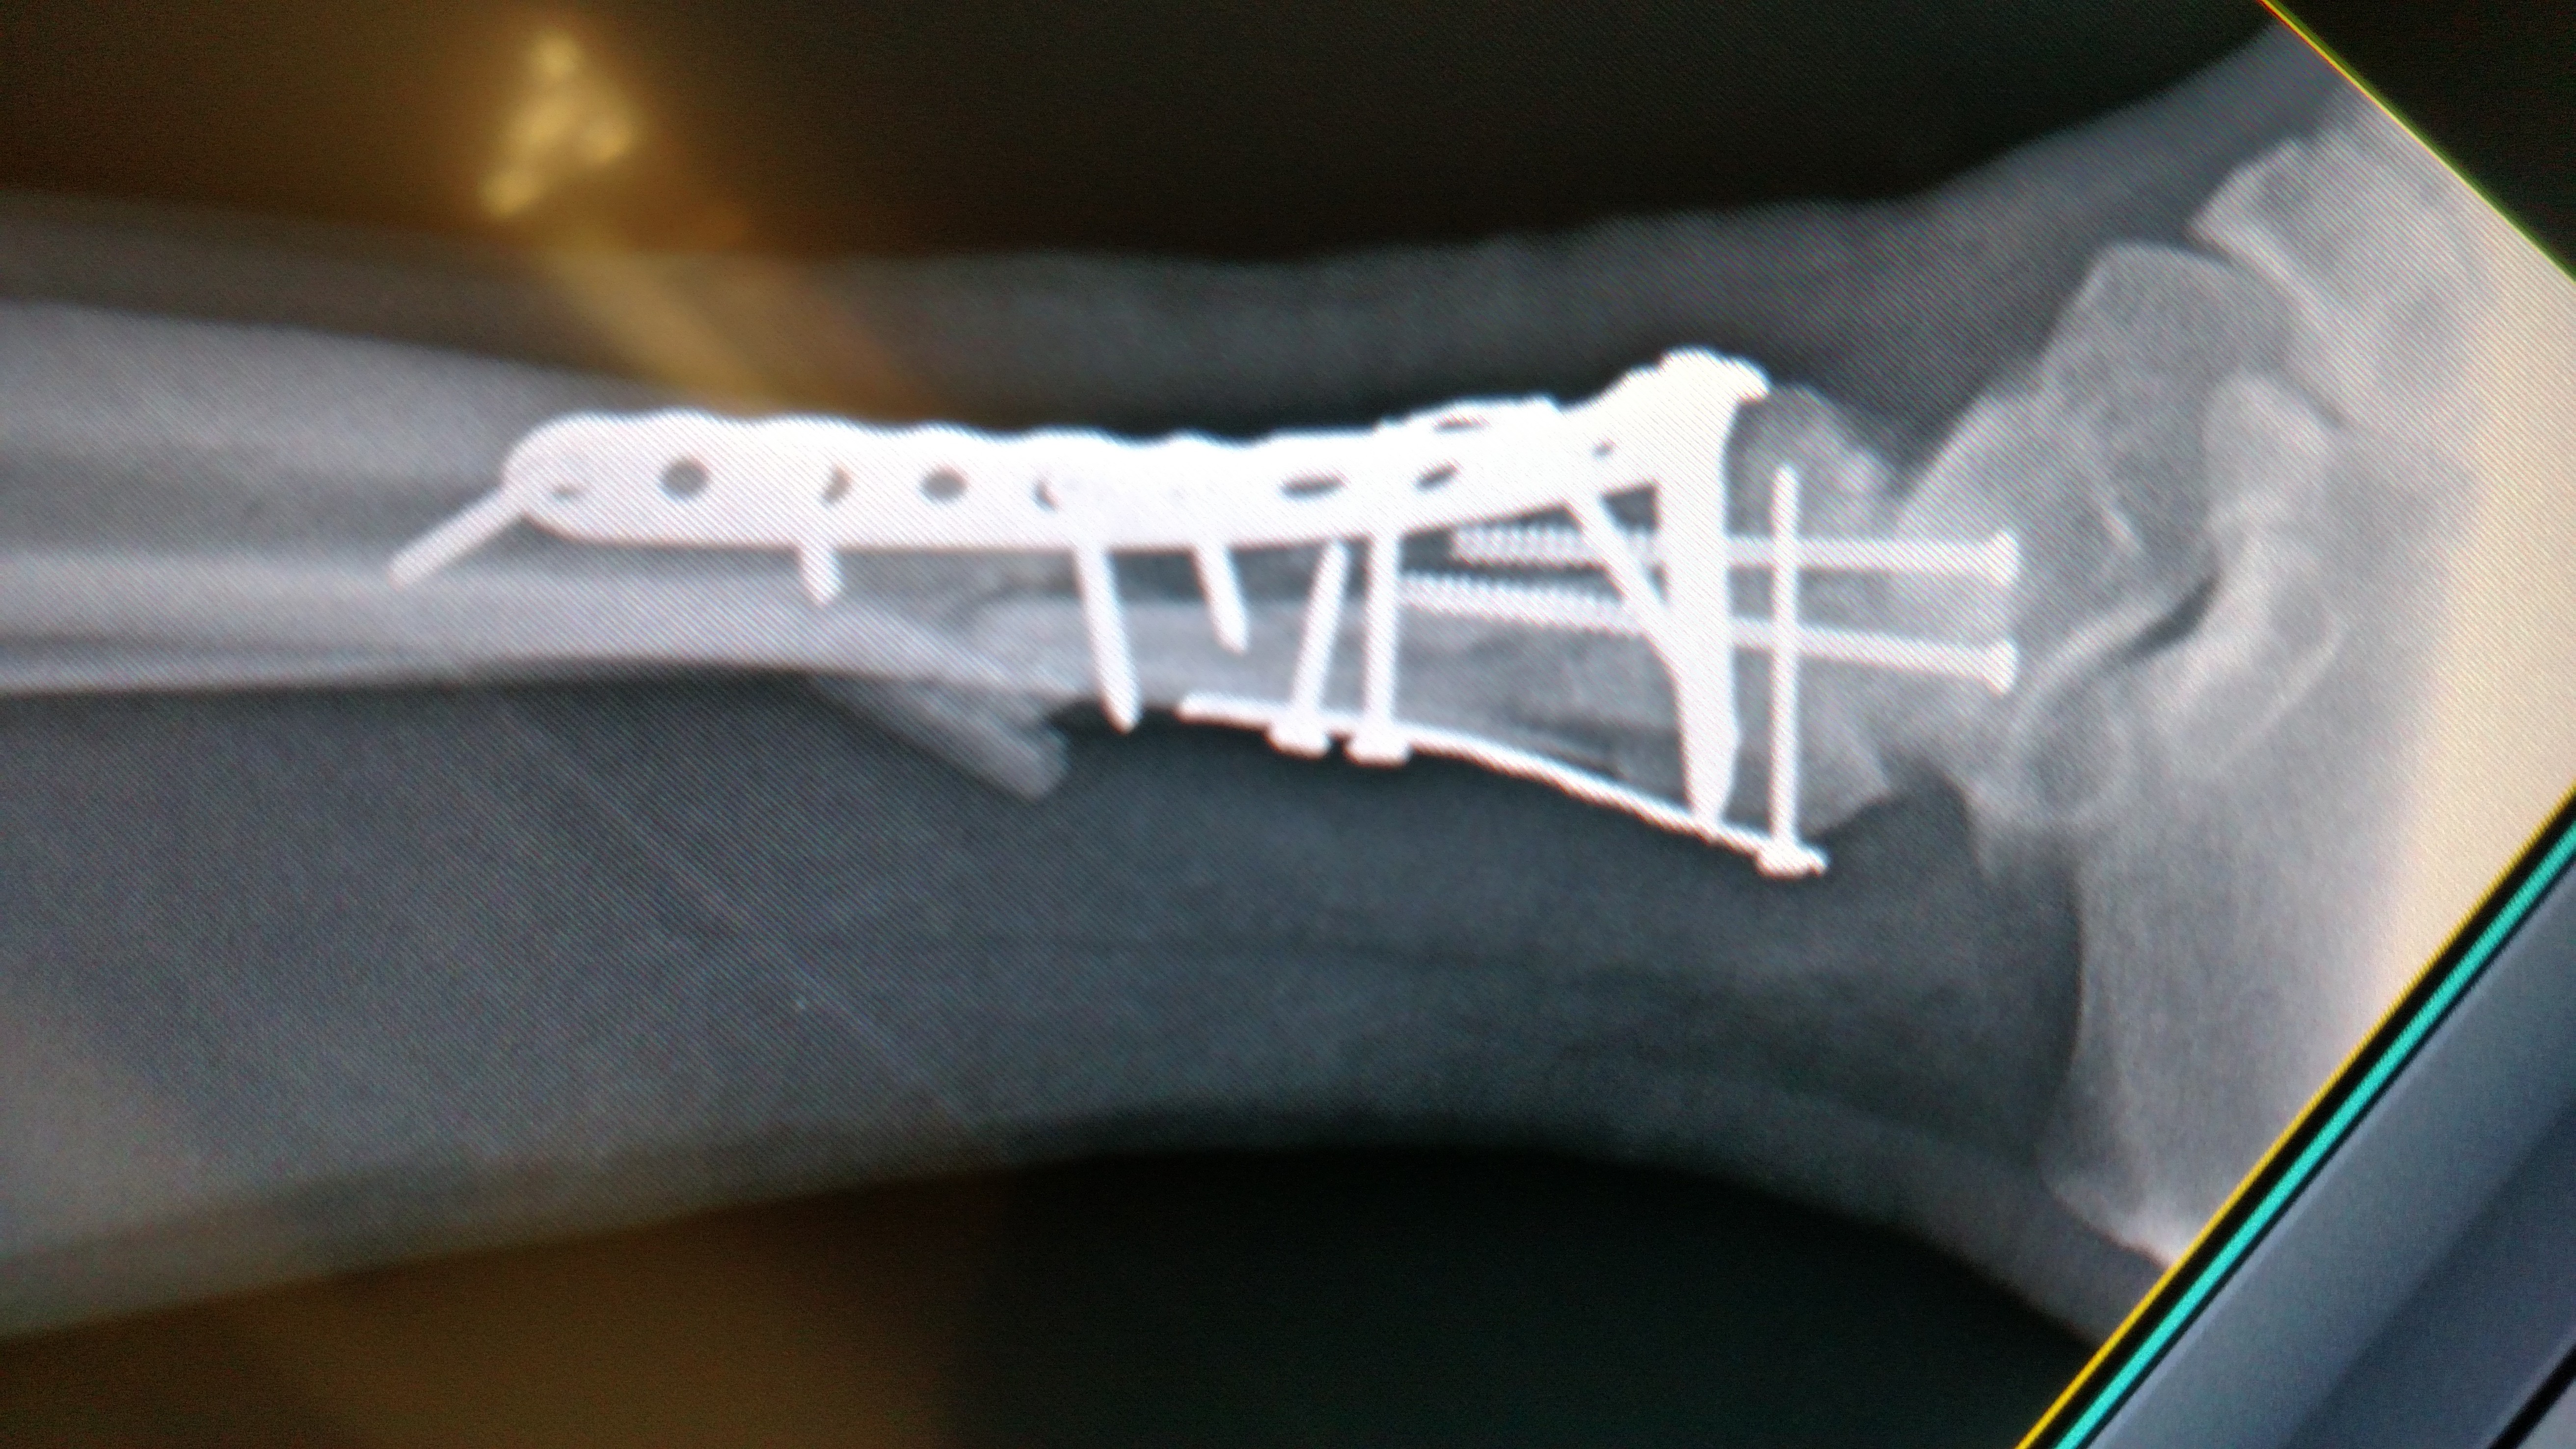

Post surgery xray Published August 20, 2015 at 5248 × 2952 in Post surgery xray My x-ray immediately post surgery